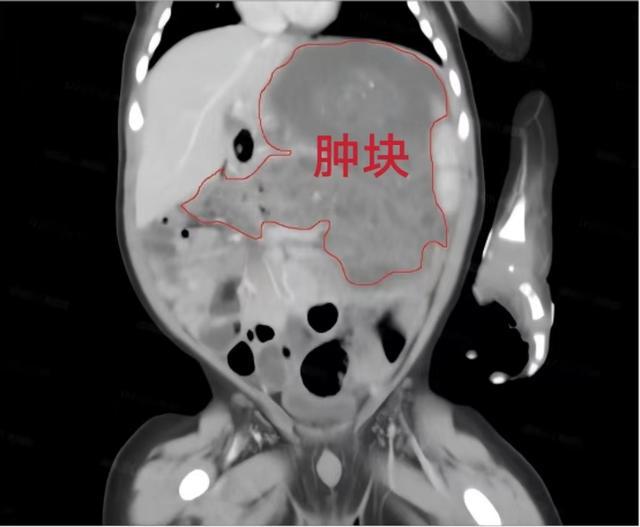

来自宁乡市的男婴小洋洋,因腹泻、排黑便在当地医院就诊治疗,腹部B超及腹部CT发现腹部有一肿块后转诊至湖南省儿童医院。

经进一步检查发现,洋洋整个左侧腹腔存在巨大占位病变,胃壁结构受侵,考虑为胃壁来源的畸胎瘤,且已压迫胃、肝脏及膈肌,并有持续增大趋势,存在破裂、出血、感染及恶变风险;同时因肿瘤压迫,洋洋吃奶缓慢、营养摄入不足,生长发育受到严重影响,手术成为唯一有效的治疗方式。

术中,团队精细分离肿瘤与周围组织,完整切除约10×8×7cm³的胃内肿瘤及胃外病灶,肿块重400克,占据洋洋身体重量的十分之一。并妥善修补胃壁,最大限度地保护了其消化道功能。手术过程顺利,洋洋生命体征平稳。